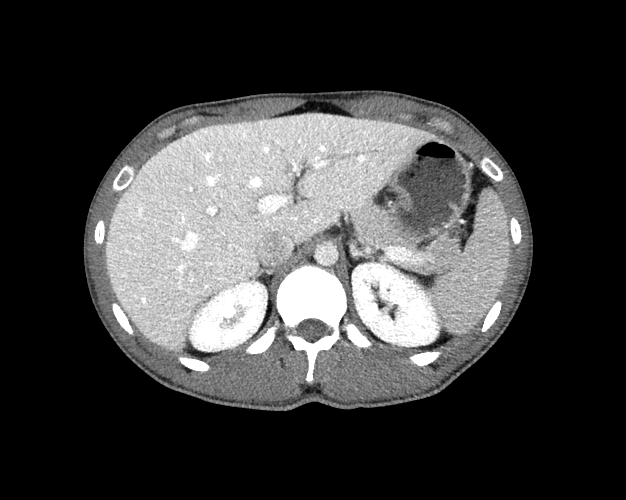

Body

Covers abdominal CT anatomy.